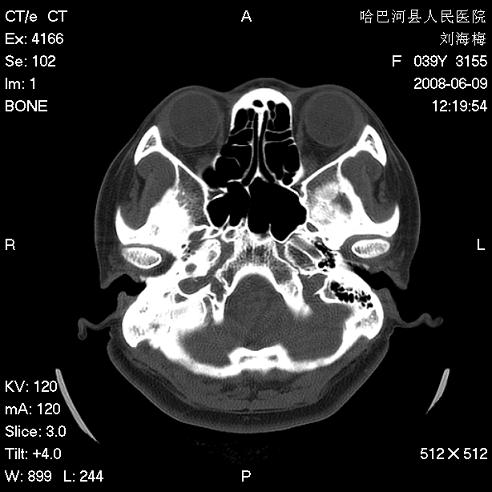

标题: CT13909:F39Y,头痛1年 [打印本页]

标题: CT13909:F39Y,头痛1年

头痛1年

枕骨蛛网膜颗粒压迹。

嗜酸性肉芽肿?骨髓瘤?不像蛛网膜颗粒压迹,太大了,并且有占位效应。

枕骨胆脂瘤

支持枕骨蛛网膜颗粒压迹。头痛与此无关。

1.应该考虑表皮样囊肿

2.右中耳乳突应薄扫!

支持枕骨胆脂瘤可能性最大。右侧乳突部密度增高,建议薄扫。